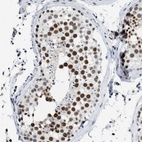

Immunohistochemistry analysis in human testis and skeletal muscle tissues using Anti-SCAF4 antibody. Corresponding SCAF4 RNA-seq data are presented for the same tissues.